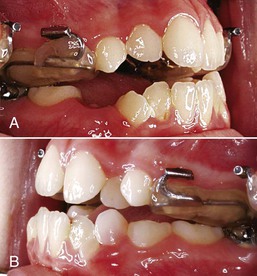

The protraction headgear force is applied via elastics to teeth or other devices supported by teeth and/or the palate. The primary aim is to transmit the force to the midface sutural interfaces. To achieve this, it is important to stabilize the maxilla as one unit (Fig. 16-1). In the primary dentition, it is advisable to use a cemented acrylic occlusal bite block or a removable acrylic plate with occlusal coverage (see Chapter 12). In patients with the mixed dentition and early permanent dentition, a removable acrylic plate (Fig. 16-2) should be used, supported by bands with headgear tubes on the molars or a rigid archwire with a palatal arch. Probably the best stabilization in patients with maxillary first molars is provided by a fixed rapid palatal expansion (RPE) device (Fig. 16-3). We prefer a Hyrax type of nonbonded device, as bonded RPEs (Fig. 16-4) interfere with the primary exfoliating teeth or teeth in the eruptive phase. Studies have also indicated that a simultaneous sutural expansion with an RPE at the start of protraction headgear treatment facilitates the anterior movement of the maxilla.19,20,26,27

Figure 16-1 A, Left and (B) right lateral views of an intraoral stabilization appliance. An acrylic bite block includes a heavy archwire to which a headgear tube is soldered. The bite block provides disocclusion to facilitate forward displacement of the maxilla and is cemented to posterior maxillary teeth.